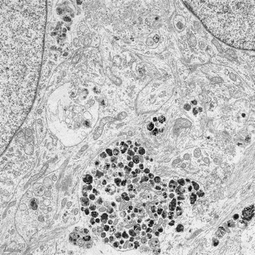

Using electron microscopy, I imaged the ultrastructure of Lewy body–like inclusions that formed in iPSC-derived dopaminergic neurons after sequential exposure to α-synuclein fibrils and proinflammatory cytokines. These inclusions were large (5–10 µm), membrane-bound, and perinuclear, resembling authentic Lewy bodies seen in PD brain tissue.This work provided the first ultrastructural evidence of Lewy body–like pathology developing in human neurons in vitro.

In this figure, I compared neurons treated with α-synuclein fibrils alone versus fibrils plus IFN-γ. Fibrils alone produced only small puncta, while the dual-hit condition drove large inclusions in cell bodies and neurites. Electron microscopy showed these inclusions packed with fibrils and organelles, closely resembling Lewy bodies and Lewy neurites in Parkinson’s disease.